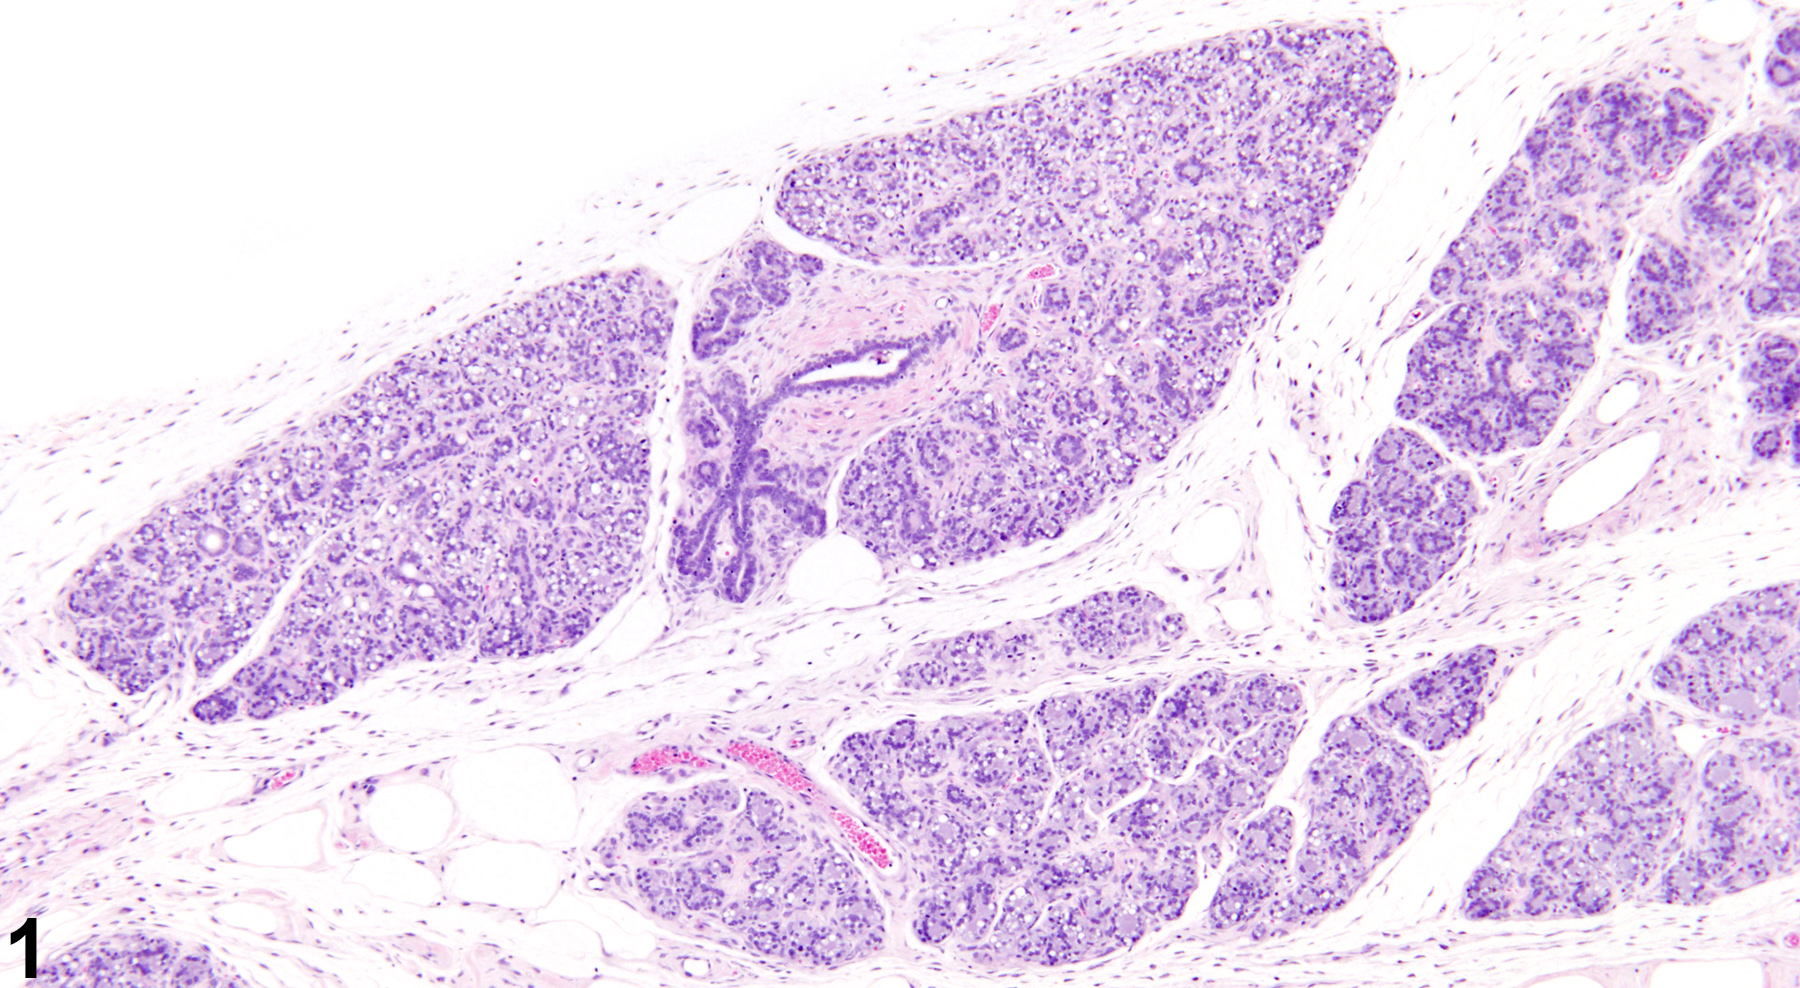

Nonphysiological, spontaneously occurring mammary gland hyperplasia of uncertain etiology is a common aging change in virgin rats and mice, and can occur in both sexes. Mammary gland hyperplasia can also result from ovarian or pituitary hormone imbalances, which can be primarily or secondarily induced by factors such as exogenous toxins and nutrient deficiencies. Hyperplasia can also be a precursor to mammary gland neoplasia (spontaneous or treatment-related). Lobular hyperplasia (Figure 1 and Figure 2) can be focal or diffuse and is characterized by enlarged lobules with increased numbers of relatively normal alveoli. Ducts are typically not affected. Depending on the amount of intraluminal secretions, the affected alveoli may have a variable diameter but are lined by a single layer of well-differentiated cells. Reactive fibrous stroma is usually present, with amounts ranging from rather scanty to more extensive. However, the lack of both compression and a prominent collagenous stroma are features that distinguish lobular hyperplasia from fibroadenoma. As well as being a treatment-related or aging change, lobular hyperplasia in females can be a physiological change occurring during pregnancy and lactation, a result of xenobiotics that cause hyperprolactinemia, as well as in pseudopregnant animals. Lobular (alveolar) hyperplasia may be a precursor of adenoma, fibroadenoma, or adenocarcinoma. However, chemically induced hyperplastic lobules do not appear to be precursors to adenocarcinoma.

Mammary gland - Hyperplasia, Lobular in a female F344/N rat from a chronic study. There are multiple enlarged lobules with increased numbers of alveoli in the mammary gland.